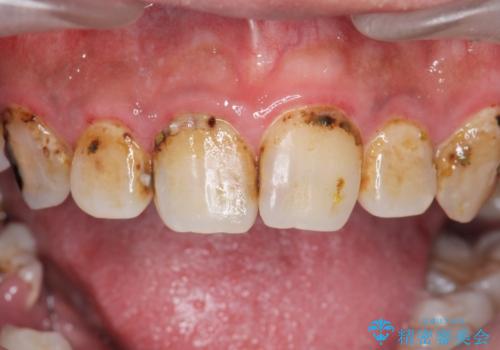

まず徹底的に虫歯を取り除き、保存が出来ない部位は抜歯(親知らずを含む)を行い、根管治療が必要な部位は精密根管治療を行いました。

その後、インプラント治療、セラミック治療を行いました。

一度治療するはを全て仮歯に変えて、歯茎を整えてからセラミックを装着しました。

また、虫歯が歯肉の中まである場合はAPF(歯肉弁根尖側移動術)も行なっています。